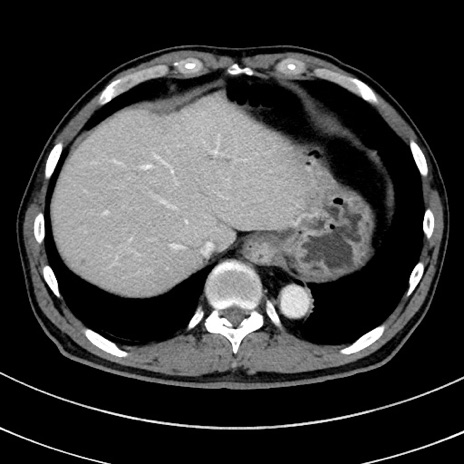

冠状断像

症例8(横断像)

【症例】 60歳代男性

【主訴】 黒色吐物

【現病歴】 4日前から嘔気自覚、2日前の朝食後にも嘔気あり、自分で手で嘔吐反射起こし嘔吐したところ血が混ざっていたため受診。

【既往歴】 5年前汎発性腹膜炎を伴う急性虫垂炎で手術、高血圧、前立腺肥大症、高脂血症

【身体所見】 腹部正中に手術癩痕あり 腹部平坦・軟圧痛なし膨満感あり

【データ】WBC 8400、CRP 4.54